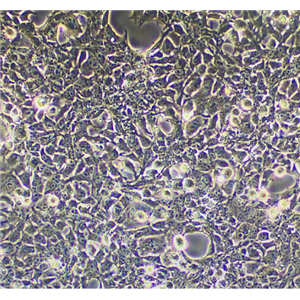

NCI-H719细胞系|人小细胞肺癌细胞是一种人小细胞肺癌细胞系,建立于1973年。NCI-H719细胞系|人小细胞肺癌细胞生长特性为半贴壁,细胞传代方法为1:2-1:3传代,每周换液2-3次。需要注意的是,该细胞系需要在低温避光的环境下保存。

NCI-H719细胞系|人小细胞肺癌细胞

(3)通过MTT实验分析不同浓度LY294002和厄洛替尼对NCI-H460、NCI-H719细胞系|人小细胞肺癌细胞和NCI-H661的细胞生长增殖的影响,同时分析联合EGFR-TKI厄洛替尼和PI3K抑制剂LY294002对NSCLC细胞生长的抑制作用;利用流式细胞仪分析厄洛替尼或LY294002以及厄洛替尼与LY294002联合用药对NSCLC细胞NCI-H460、NCI-H719细胞系|人小细胞肺癌细胞和NCI-H661细胞凋亡的影响;提取厄洛替尼或LY294002以及厄洛替尼与LY294002联合用药处理后的NCI-H460和NCI-H661细胞的总蛋白,利用蛋白免疫印迹(Western Blot)技术检测PI3K/AKT信号通路相关蛋白p70S6K和磷酸化p70S6K蛋白的表达水平。